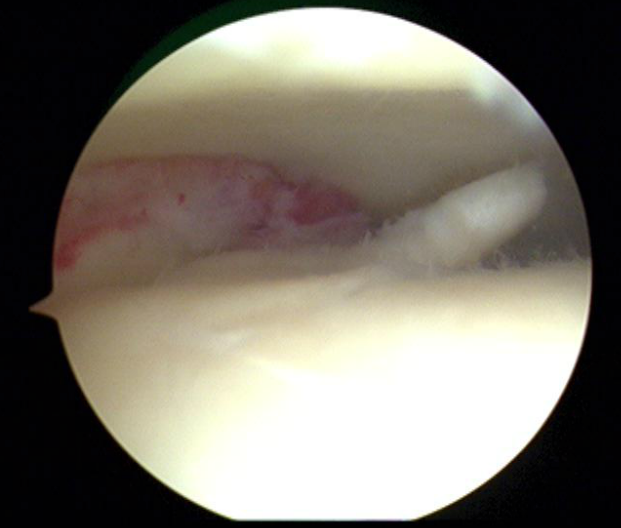

Indien nodig voert de orthopedisch chirurg een kijkoperatie van de enkel uit (arthroscopie). Via kleine steekgaatjes brengt hij een camera en werkinstrumenten in het gewricht. Het zieke kraakbeen wordt verwijderd en het onderliggende bot wordt voorbereid om het ontstane gat terug op te vullen met “litteken-kraakbeen” (fibro-cartilago).

Grote kraakbeen defecten dienen soms via andere technieken aangepakt te worden. De twee meest toegepaste chirurgische behandelingen bij een groot osteochondraal letsel in de enkel (meestal de talus of sprongbeen), zijn een OATS-procedure en een AMIC-procedure.

Bij een OATS-procedure wordt een cilinder bot- en kraakbeen uit de knie (of enkel zelf) geboord, om dan getransplanteerd te worden in het kraakbeen defect in de enkel. Dit is een veel gebruikte techniek met prima resultaat.